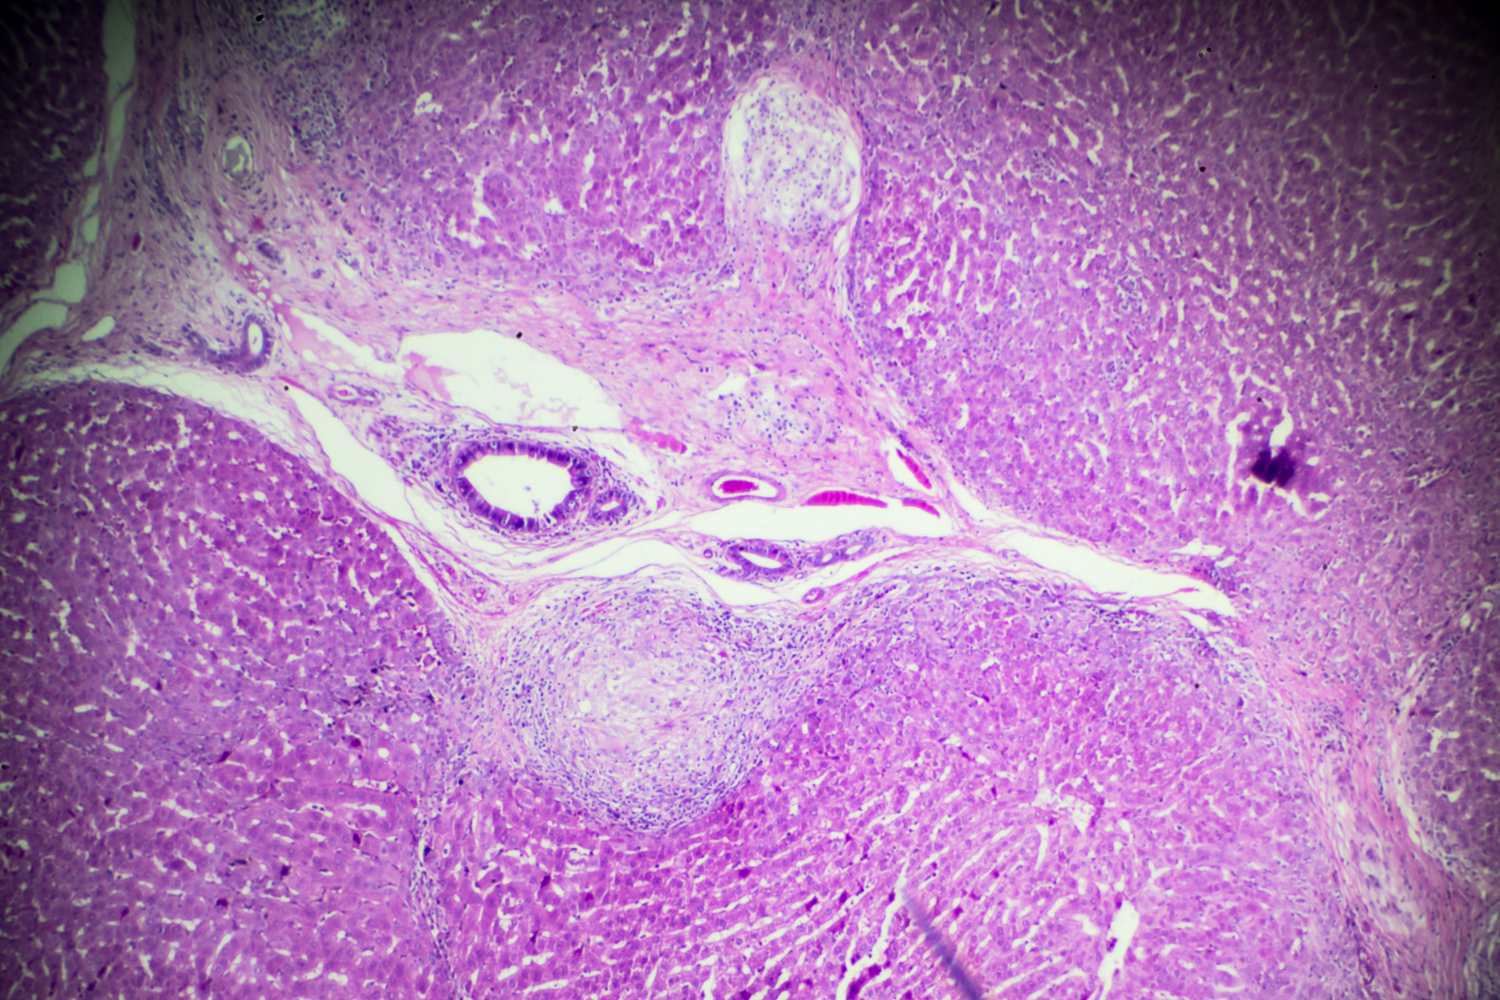

In de eerste paar uur na de infectie ontwikkelen sommige mensen een dermatitis die ‘zwemmersjeuk’ wordt genoemd, met kleine rode vlekjes op de huid. Na vier tot zes weken, wanneer de wormen eieren beginnen te leggen, verschijnen er ernstiger symptomen: koorts, spierpijn, hoesten en bloederige diarree. Eieren die vast komen te zitten in weefsels veroorzaken chronische ontstekingen.

Door de jaren heen kan schistosomiasis blijvende schade aan de lever, darmen, blaas en andere organen veroorzaken, terwijl bij kinderen de chronische infectie de groei en cognitieve ontwikkeling schaadt. De ziekte kan worden behandeld met praziquantel, een goedkoop en effectief antiparasitair medicijn, hoewel gevallen van herinfectie in endemische gebieden zeer frequent voorkomen.